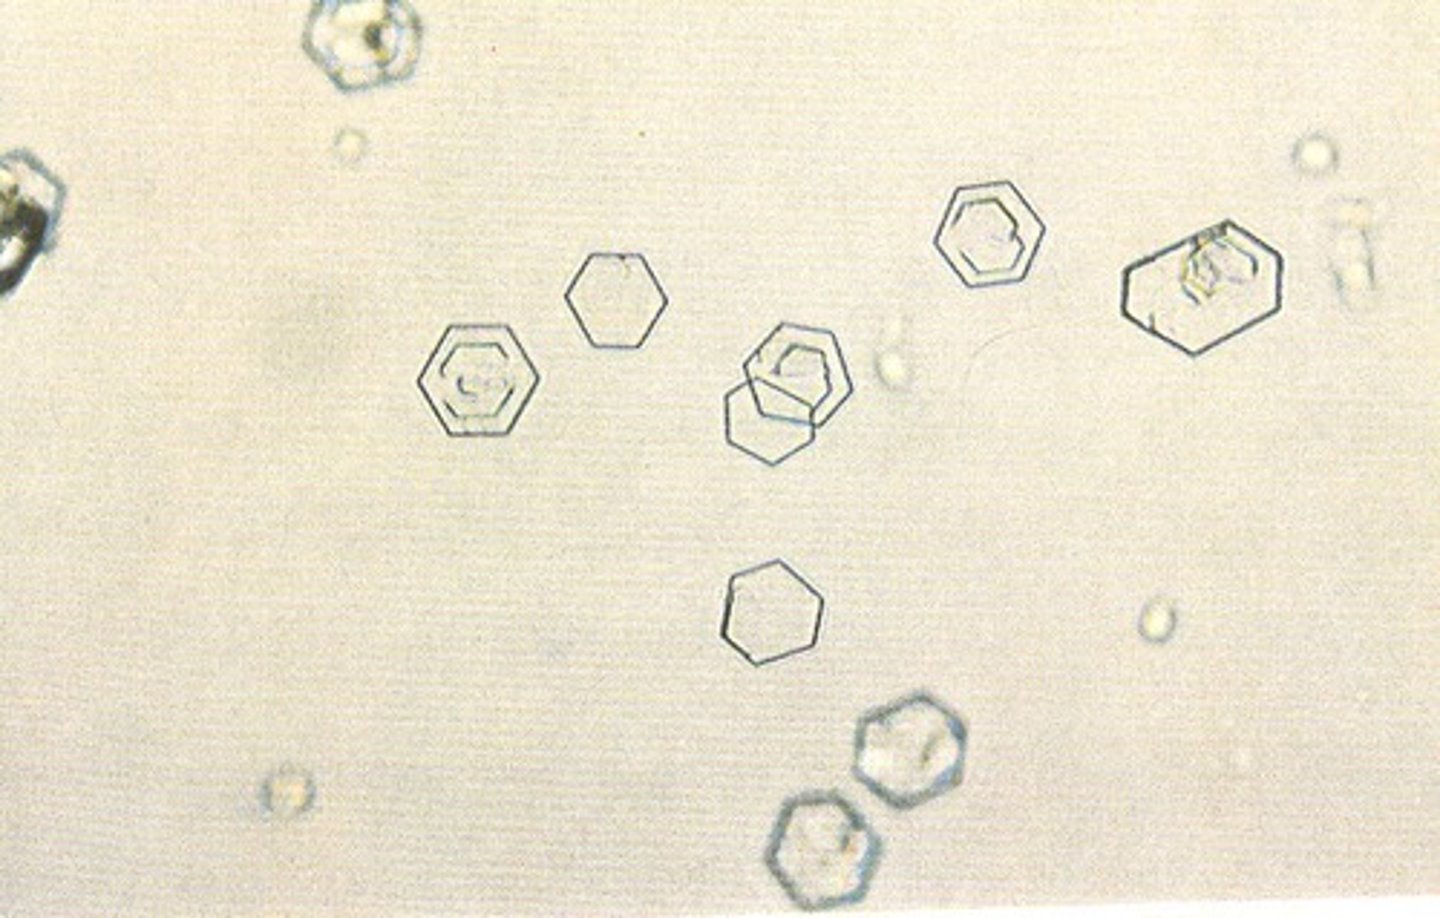

cystine crystals

urine

6 sided, hexagonal, colorless